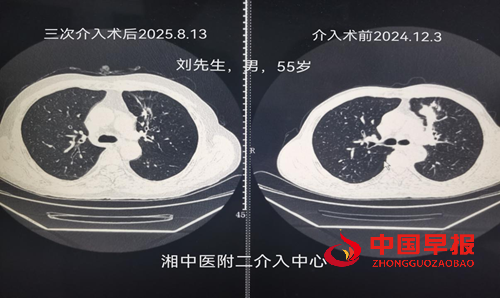

病例一:刘先生,男,55岁,患肺癌,经过三次介入微创手术+三次细胞治疗+靶向治疗,肺癌缩小90%,全身脊柱转移灶得到控制硬化,全身剧痛消失,处于NED状态。